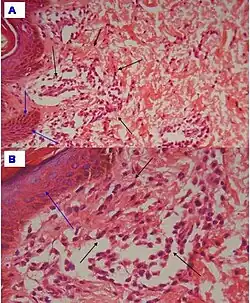

| Urticaria, lymphocyte predominant | Perivascular location. Mast cells are relatively sparse, potentially demonstrated with special stains, preferably tryptase stain. Extravasated erythrocytes are present in about 50% of the cases. No vasculitis.[14] | Dermal edema [solid arrows in (A,B)] and a sparse superficial predominantly perivascular and interstitial infiltrate of lymphocytes and eosinophils without signs of vasculitis (dashed arrow).[15]

|

| Urticaria, lymphocyte predominant | Perivascular location. Mast cells are relatively sparse, potentially demonstrated with special stains, preferably tryptase stain. Extravasated erythrocytes are present in about 50% of the cases. No vasculitis.[14] | Dermal edema (solid arrows) and a sparse superficial predominantly perivascular and interstitial infiltrate of lymphocytes and eosinophils (dashed arrow)